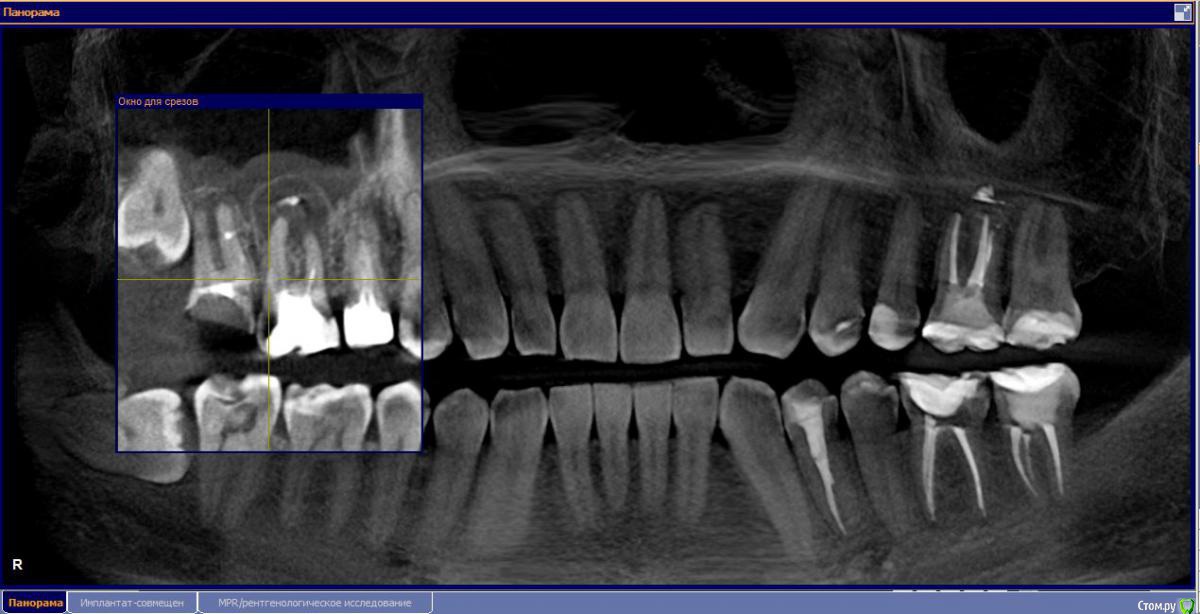

М, 33 года. Есть показания к одновременному удалению 16-го зуба - киста, и 17-го - разрушена верхушка. 8-й предлагают оставить, чтобы "держал кость" (как то так мне озвучили).

Через 3-4 месяца рекомендуют синус-лифтинг и установку двух имплантатов.

- Возможно ли консервативное перелечивание 16 зуба и есть ли смысл?

- Насколько опасная имеется киста?

снимки прилагаю.

и 6 и 7й зубы не выглядят 100% кандидатами на удаление.

1.6 большая вероятность сохранить,но понятнее при очном осмотре и диагностическом вскрытии. 1.7,скорее всего,не жилец,но тоже очно взглянуть на него стОит